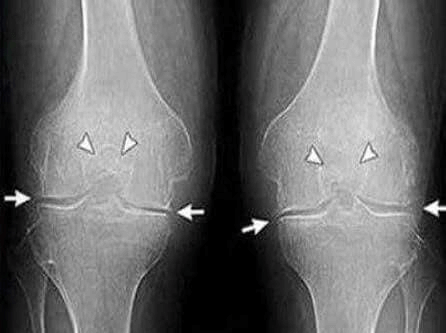

Rendgen sa očiglednim znacima artroze